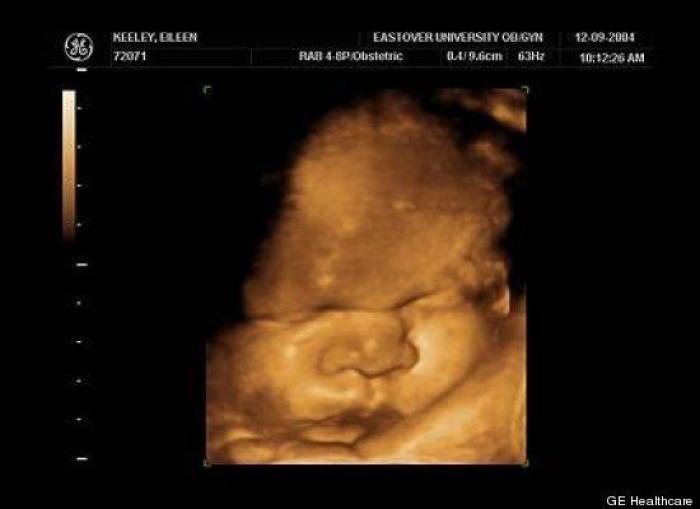

En esta galería puedes ver en fotos como es el desarrollo de un feto de semana en semana:

Desarrollo del feto, en fotos

Ver la galería